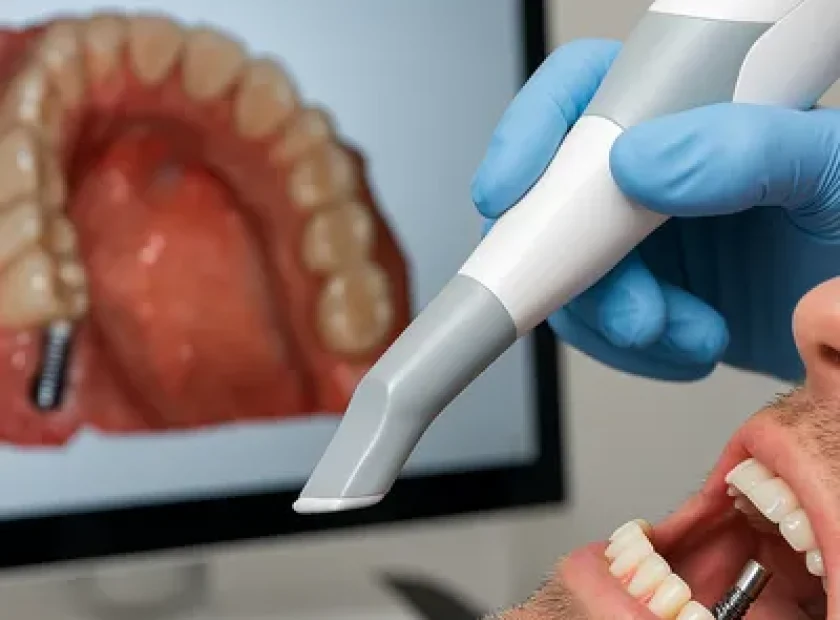

قالبگیری دیجیتال: در ایمپلنت یکروزه این مرحله بلافاصله پس از کاشت انجام میشود و نیازی به انتظار برای ترمیم لثه نیست.